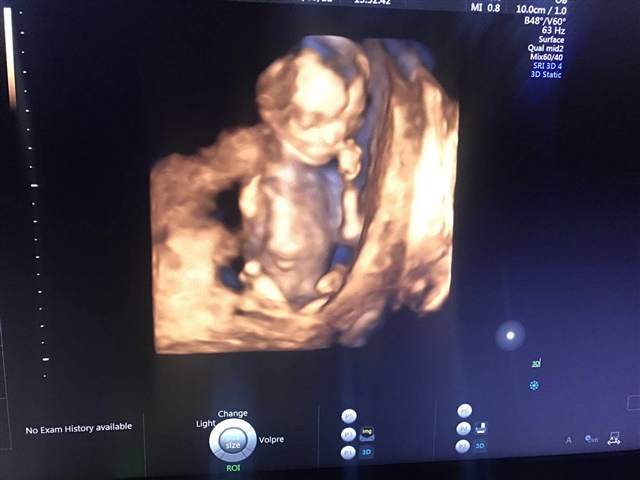

孕10周+1天

孕29周+1天

孕22周+1天

孕24周+2天